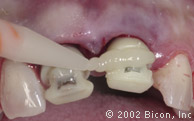

Подготовка к установке постоянной конструкции

Произведены послабляющие разрезы

Установка готовых конструкций